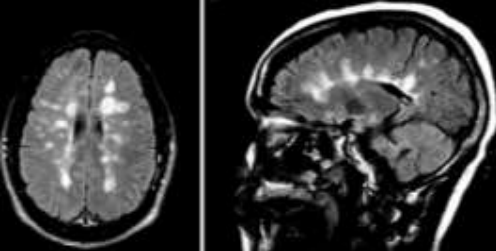

Assinale a alternativa que descreve corretamente o sinal radiológico abaixo e o possível diagnóstico a ele associado.

Provas